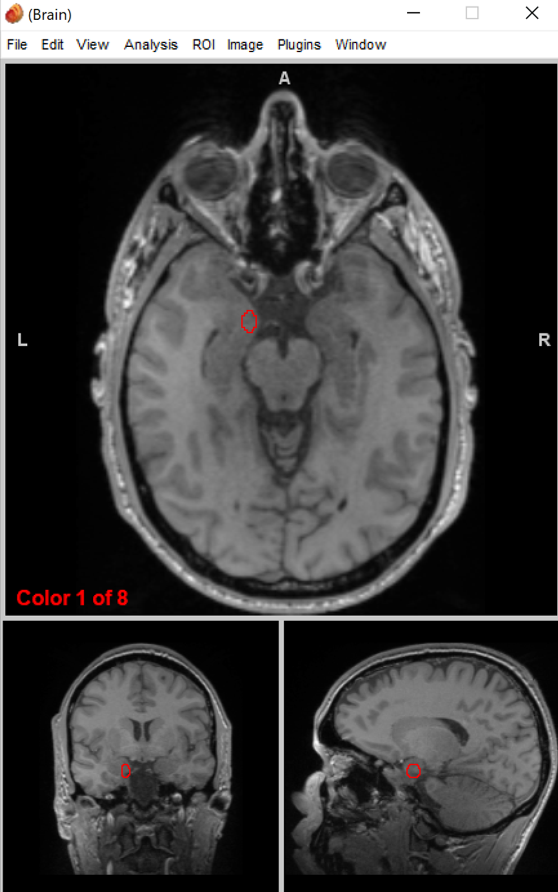

optic chiasm

separates visual input